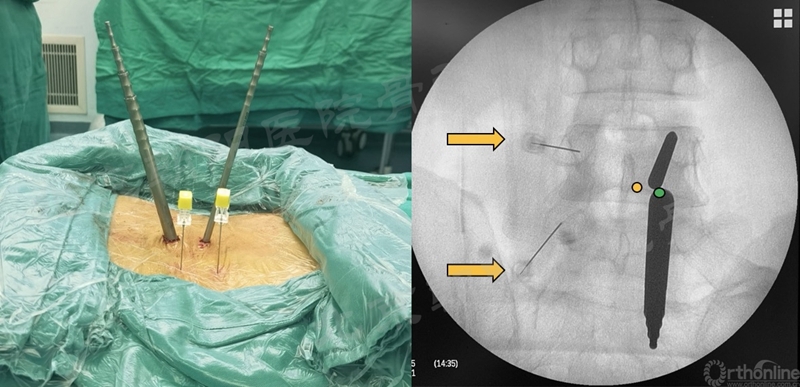

在经历15例UBE减压手术的学习曲线后,本团队进行了UBE腰椎减压融合术:#16例UBE,L4/5 LSS。

UBE-LIF手术步骤大致按常规开放手术:

1、显露L4椎板下缘-L4/5关节突-L5椎板上缘;

2、Kerrison钳减压L4下关节突(全部去除)-L5椎板上缘-L5上关节内侧缘(尽量靠外)-黄韧带整体切除;

3、硬膜外止血,显露椎间盘,确定椎间隙位置和方向;

4、椎间隙处理:骨刀,髓核钳,终板刮刀,Kerrison钳,电凝,+耐心;

5、自体骨+同种异体骨植骨;

6、可撑开融合器植入(透视定位);

7、检查遗漏的骨块,彻底清除神经周围的致压物;

8、必要时做对侧黄韧带减压;

9、经皮植入椎弓根螺钉,加压固定。

术前MRI和术中定位

椎间隙处理

植入可撑开Cage

术后X线片与CT(矢状面)

术前、术后MRI及CT(轴位)